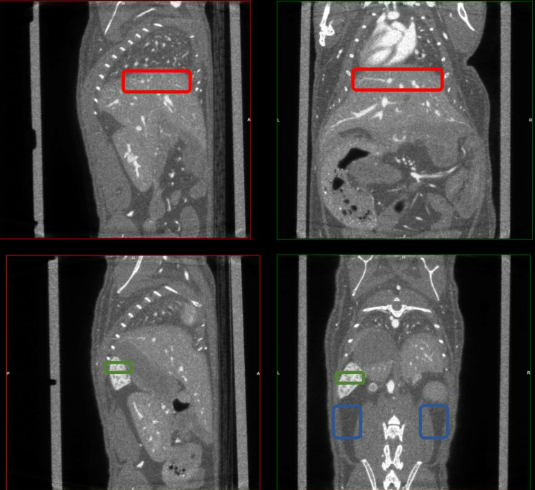

Our latest publication on “Novel in vivo micro-CT Imaging Techniques for Assessing the Progression of Non-Alcoholic Fatty Liver Disease” is now available online.

A rewarding collaboration with Antonios Chatzigeorgiou, Anna Hadjihambi and Rallia Velliou. Whenever setting up a new procedure at BIOEMTECH Labs, we always consult JoVE as a gold-standard basis of precise workflows, so it is of great honor and pleasure to have our own protocol under their list of standardized procedures. Also, using non-invasive in vivo imaging techniques to evaluate the progression or the therapy efficiency over a pathology, is one of greatest strengths of preclinical research and always intriguing to evaluate and establish into an actual preclinical platform.